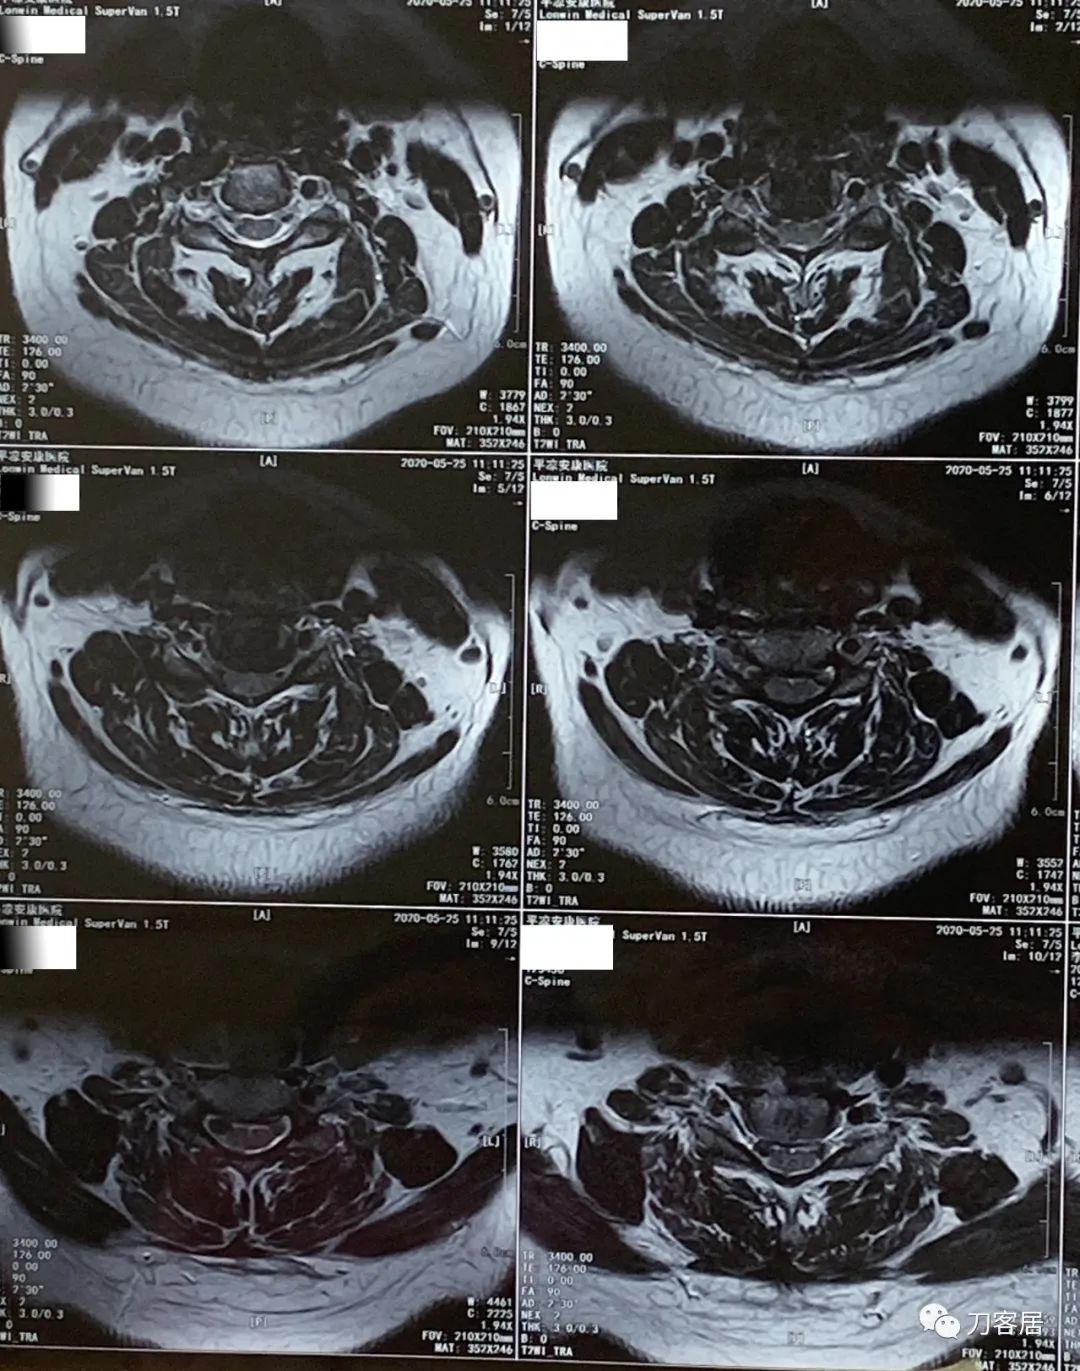

患者回当地后,一直没有再去医院就诊,不过到了2021年5月4日,患者在当地又做了一次颈椎磁共振检查。也就是经过抗骨质疏松治疗后,患者的临床症状应该都没了,恢复了正常的生活,从2020年8月19日到2021年5月4日,将近9个月,患者没有再去医院看病,到了2021年5月4日,患者又做颈椎磁共振,应该是患者自行停药,颈肩痛的症状又来了,然后到当地医院就诊,仍然考虑颈椎病,给开了颈椎磁共振检查。

图22. 20210504美年大健康平凉分院颈椎MRI01

图23. 20210504美年大健康平凉分院颈椎MRI02

图24. 20210504美年大健康平凉分院颈椎MRI03

图25. 20210504美年大健康平凉分院颈椎MRI04

图26. 20210504美年大健康平凉医院颈椎MRI报告